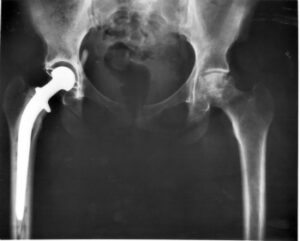

Full Hip Replacement

Full hip replacement can involve one or both hips. This process involves replacing the bones making up the ball and socket of the hip-joint. These bones can either be replaced with metal, ceramic, or plastic parts.